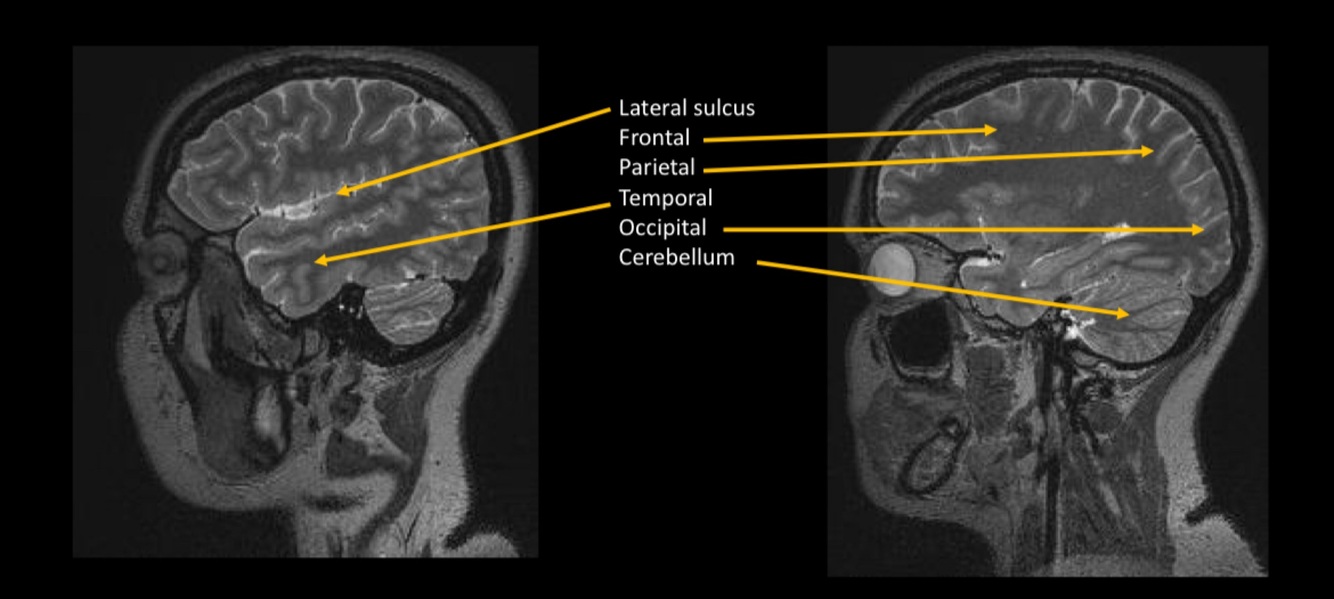

In this image we can see the…

Sylvian sulcus